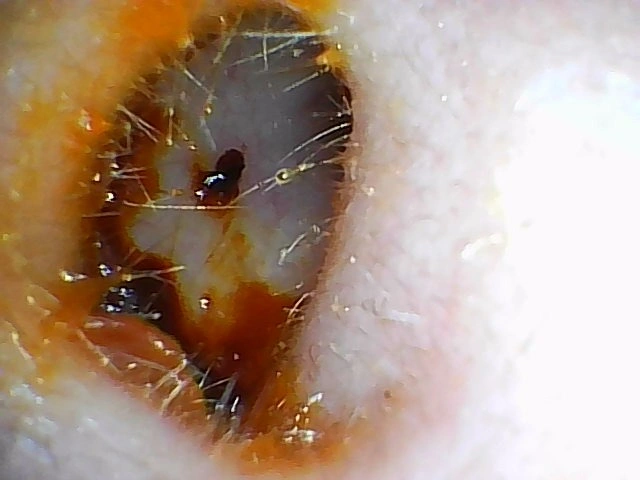

Frequently Asked Questions about Ear Wax

A: Professional ear wax removal performed by certified audiologists at our Capalaba and Hamilton clinics is generally comfortable and pain-free. You may experience mild pressure sensations during the procedure, but it shouldn't be painful. If you have sensitive ears, inform our audiologists so we can ensure maximum comfort.

A: We strongly advise against attempting DIY ear wax removal, especially for impacted wax. Over-the-counter ear drops may help soften minor wax buildup, but removal should always be performed by trained professionals. Home removal attempts often push wax deeper or cause injuries.

A: The ear wax removal procedure typically takes 15-30 minutes, depending on the amount of impacted wax. Your complete appointment, including ear examination and aftercare instructions, usually requires 45-60 minutes at both our Queensland locations.

A: Most patients at our Capalaba and Hamilton clinics experience immediate hearing improvement. You'll likely notice reduced muffled sounds, eliminated ear fullness, and clearer hearing right after the procedure.